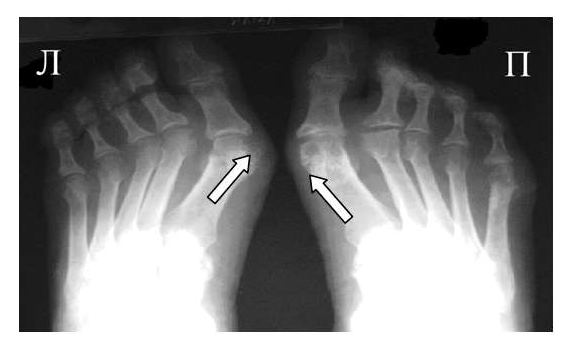

Рис. 2 Симптом «пробойника» в головках плюсневых костей обеих стоп в сочетании с вальгусной девиацией I плюсне-фаланговых суставов

Эрозии часто обнаруживаются в верхней и медиальной части плюсневой головки и часто в сочетании с вальгусной девиацией суставов. Типичным является асимметричность изменений (рис. 2).

При развернутой картине болезни деструкция концевых фаланг (акроостеолиз) и чашеобразная деформация проксимальной части фаланг пальцев кистей вместе с концевым сужением дистальных эпифизов симптом «карандаш в колпачке» (рис. 5), множественный остеолиз и деструкции эпифизов костей с разнонаправленными деформациями суставов (мутилирующий артрит).

Часто при псориазе рентгенологические проявления в мелких суставах кистей и стоп сочетаются с воспалительными изменениями крестцово-подвздошных сочленений сакроилиитами, обычно двусторонними асимметричными или односторонними.